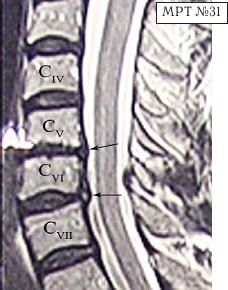

МРТ № 31

Он взял отпуск и поехал в Москву в довольно известную частную клинику. Прошёл курс лечения, который включал в себя «стандартный набор»:

— мануальную терапию, с целью уменьшения (устранения) болевого синдрома, путём восстановления соотношений суставных поверхностей дугоотростчатых суставов в сегментах CV-CVI и CVI-CVII (устранение сублюксации);

После обследования у него было обнаружено:

— абсолютный стеноз спинномозгового канала шейного отдела позвоночника с полным блоком ликворных путей и сдавлением дурального мешка спинного мозга на уровне сегментов CV-CVI и CVI-CVII;

— в сегменте CV-CVI — значительный спондилёз, гипертрофия задней продольной связки, и практически компенсированная спондилёзом грыжа межпозвонкового диска;

— в сегменте CVI-CVII — довольно активная грыжа межпозвонкового диска;

— на уровне поражённых сегментов выраженный эпидурит.